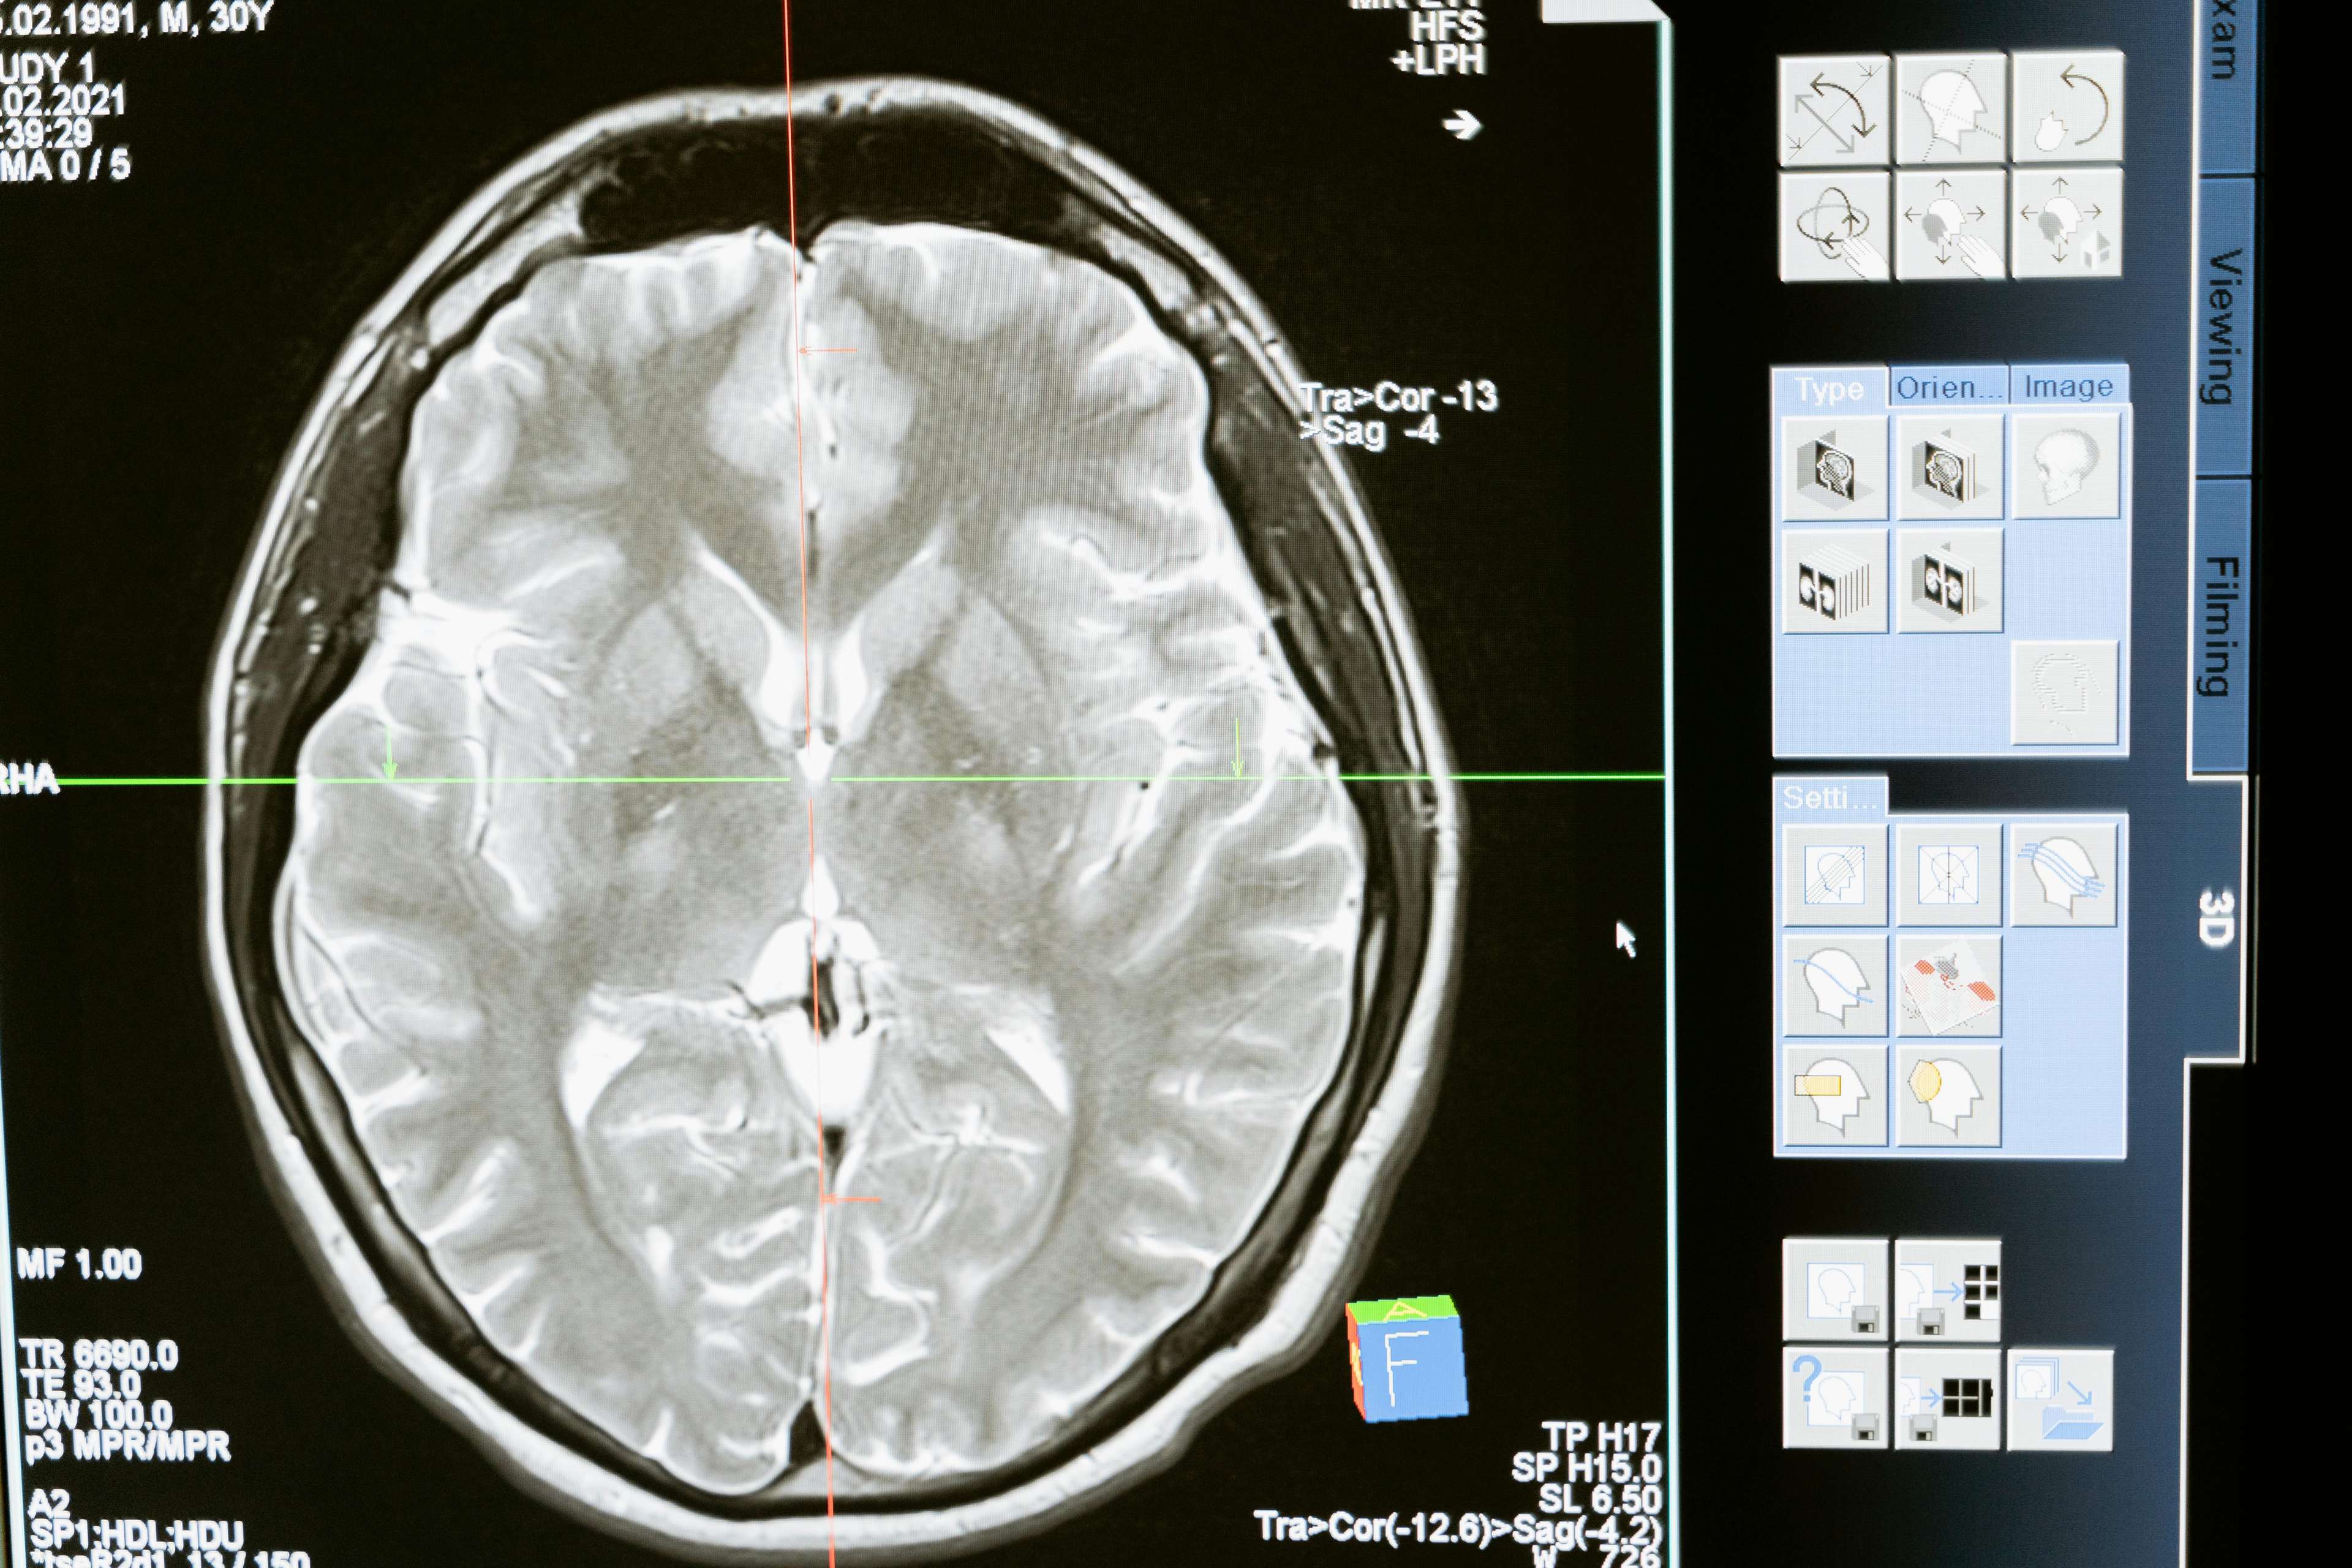

Deep brain stimulation is a surgical procedure that involves implanting a device that sends electrical impulses to specific areas of the brain. This innovative treatment has been instrumental in managing a range of conditions, including Parkinson's disease, dystonia, obsessive-compulsive disorder, and epilepsy. By targeting specific areas of the brain, deep brain stimulation can help regulate abnormal brain activity, alleviating symptoms and significantly improving quality of life. The results are nothing short of remarkable – patients who were once confined to their homes are now able to walk, run, and live life to the fullest.